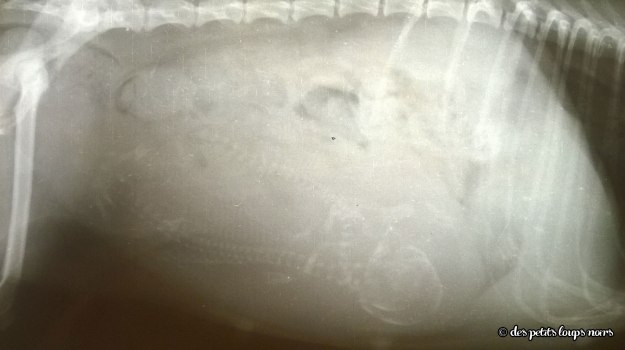

Dune de sable et Coyotte ont donné naissance le 31 octobre 2014 à 2 adorables puce fauve, charbonnées :

- Juanita banana des petits loups noirs ;

- Java d’enfer des petits loups noirs